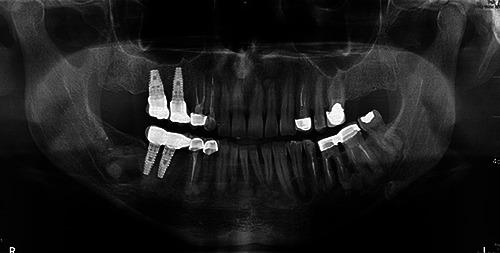

Florid cemento-osseous dysplasia (FCOD) is a rare benign fibro-osseous lesion which affects multiple quadrants and predominantly the mandible. This case report presents a successful implant placement with 8-year of follow-up in a 44-yearold woman asking for a fixed restoration in mandibular right posterior edentulous area. Radiographic images showed lobular, irregularly shaped radiopacities and radiolucencies almost symmetrically observed in the premolar-molar area of the right and left regions of the mandible. The findings of Xray images were attributable to FCOD. Minimally invasive two-stage surgery with strict infection control was followed to place two implants in lower right posterior region. The implants demonstrated clinically rigid fixation and restored successfully after 6 months. A direct functional connection between dysplastic bone and the implant load bearing surface was evidenced by the lack of symptoms, and the lack of soft tissues inflammation or peri-implant bone loss up to 8 years follow-up.

florid骨水泥骨发育异常(FCOD)是一种罕见的良性纤维骨病变,累及多个象限,主要累及下颌骨。本病例报告介绍了一名44岁女性在下颌右后牙无牙区进行固定修复,成功植入种植体并随访8年的情况。影像学图像显示在下颌左右区域的前磨牙-磨牙区几乎对称地观察到小叶状、形状不规则的不透射线区和透射区。X线图像的表现符合FCOD。采用严格控制感染的微创两阶段手术,在下颌右后区域植入两颗种植体。种植体在临床上表现出坚固的固定,并在6个月后成功修复。在长达8年的随访中,没有症状,没有软组织炎症或种植体周围骨丢失,证明发育异常的骨与种植体承载表面之间存在直接的功能连接。